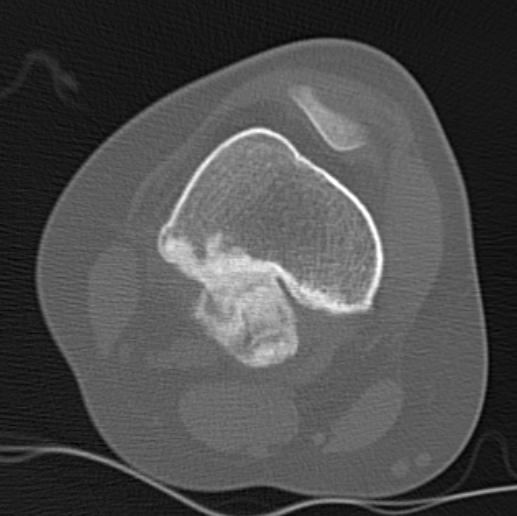

CT

Can be used to differentiate from osteochondroma

1. Parosteal OS

- attached to cortex growing into soft tissue

- normal cortex intact

Parosteal Osteosarcoma proximal tibia